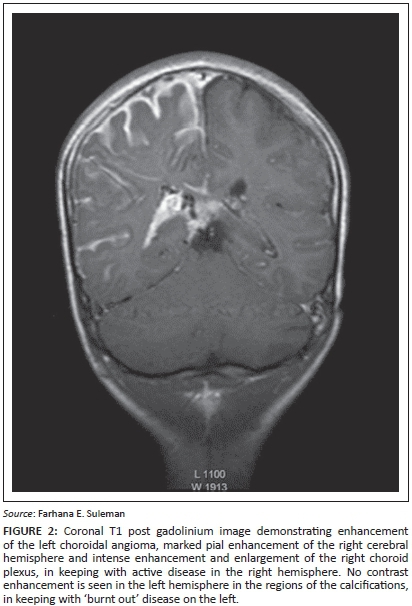

Magnetic resonance imaging (MRI) post contrast enhancement is the most accurate imaging study to demonstrate the extent of the pial enhancement, as cortical calcifications usually mask the degree of enhancement on computed tomography (CT) scans. The choroid plexus is frequently enlarged with a positive correlation to the extent of the leptomeningeal angioma (Figure 2). The underlying white matter typically shows accentuated T2 shortening.7